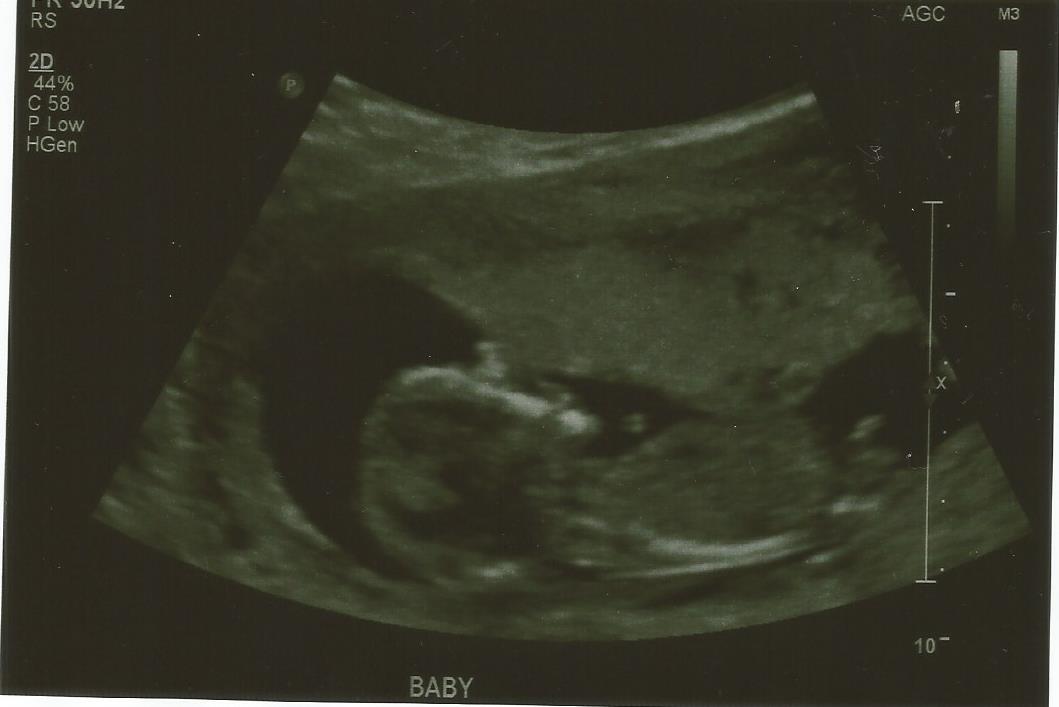

Boy guess

Anyone else having any guesses? I'm still finding it hard to believe that the pointy thing sticking up is a boy part. I have three girls and each time people thought I was having a boy and it was girl. I'm driving myself insane with it.